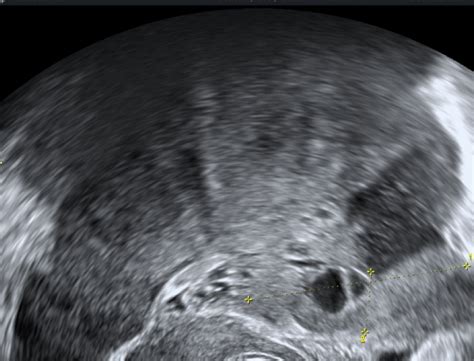

Diagnostika PCO temelji na ultrazvočni sliki jajčnikov, ki kažejo 8 ali več ločenih foliklov, pri čemer stroma zavzame 25% ali več celotnega jajčnika. Pogosto so ti jajčniki povečani. Poleg tega se upoštevajo tudi znaki oligo- ali amenoreje (redka ali odsotna menstruacija) ter klinični znaki hiperandrogenizma (npr. hirsutizem - prekomerna poraščenost moškega tipa).